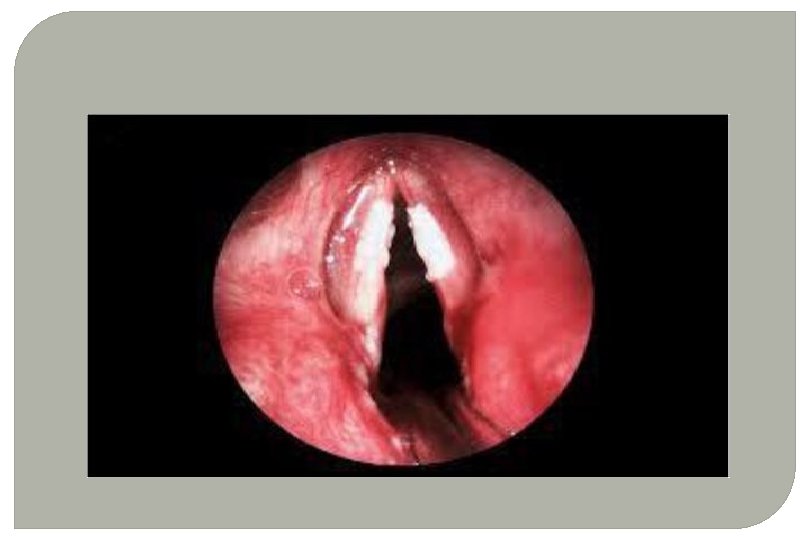

• Hyperaemia of laryngeal structures. • Vocal cords appear dull red • Rounded flecks of viscid mucus are seen on the vocal cords and interarytenoid area.

• Dusky red, thickened laryngeal mucosa • Vocal cords appear red and swollen - later may be irregular & nodular • Ventricular bands appear red and swollen • Mobility of cords impaired - oedema & infiltration, later muscular atrophy /arthritis of the cricoarytenoid joint